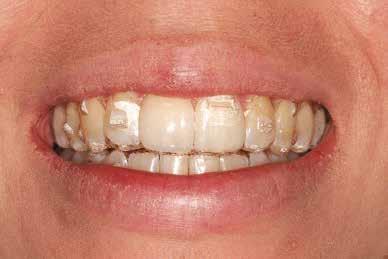

8. a-b. ábra: A páciens a felső első kisőrlő palatinális csücskének elcsiszolása előtt (a) és (b) után, a szemfogvezetés kialakításához. A szemfog vesztibuláris felszínének befejezése.